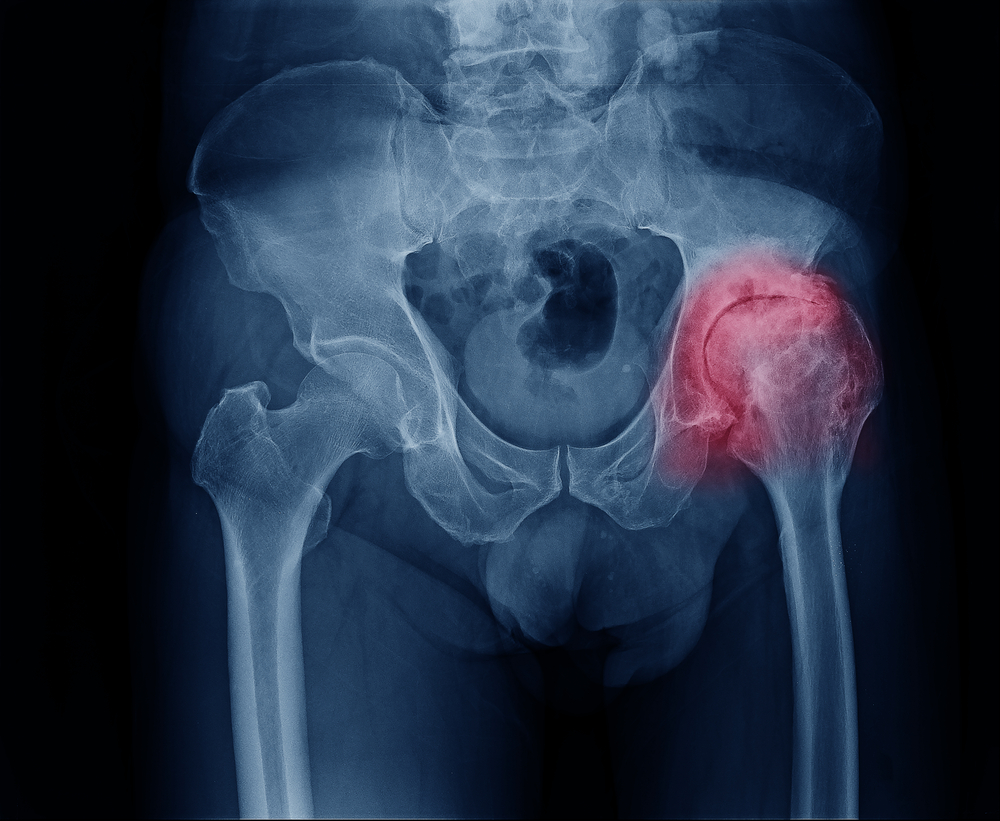

- Артроз — изменения в хряще (деструктивные), далее его разрушение и изнашивание. Но патологическим видоизменениям в этом случае, из-за несвоевременного обращения подвергается и сама костная ткань.

- Ревматизм — воспалительный процесс, который сосредоточен в суставах.

- Рентген и УЗИ – показывают, есть ли инфекционные посылки, возможные артриты, артрозы.

- Рентген и УЗИ. С их помощью диагностируются артрозы, артриты, инфекционные поражения костей.

- Переломы шейки бедра сопровождаются неярко выраженной отечностью, болевыми ощущениями в области тазобедренного сустава, паха. Кровоподтеков практически нет.